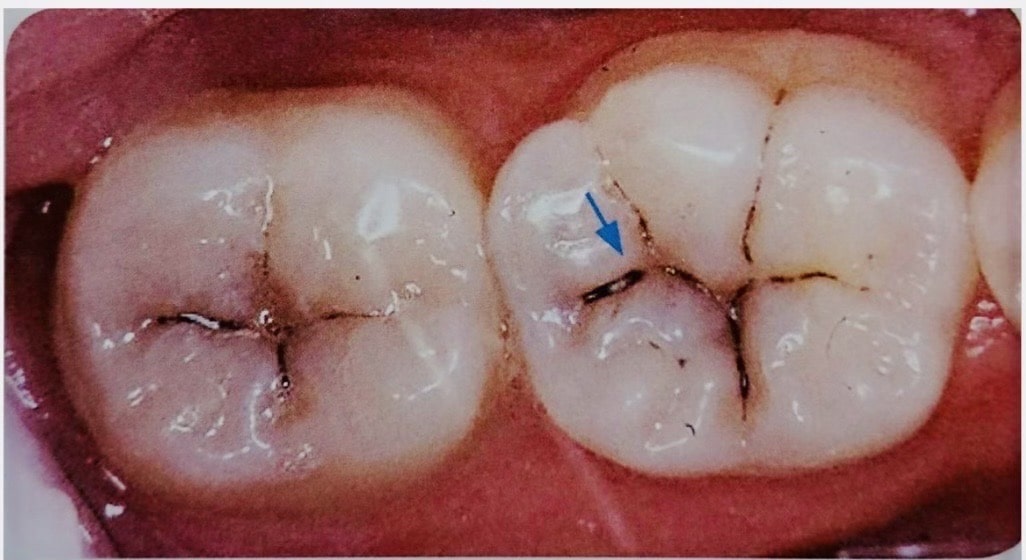

虫歯が疑われたが削らずに済んだ例

視診では歯間部が黒く透けており虫歯が疑われ治療が必要そうな状態 |

レントゲンでは虫食い状に黒く写ってはないので深く虫歯は進行してはいないと判断した |

レーザー診断にて数値が「40」だったため『初期虫歯』と判断し、削らず経過観察とした。 |

このように数値で虫歯の進行状況がわかるため、なるべく削らない治療が可能です。

当院では61以上の数値で治療が必要と判断します。

視診では歯間部が黒く透けており虫歯が疑われ治療が必要そうな状態

レントゲンでは虫食い状に黒く写ってはないので深く虫歯は進行してはいないと判断した

レーザー診断にて数値が「40」だったため『初期虫歯』と判断し、削らず経過観察とした。